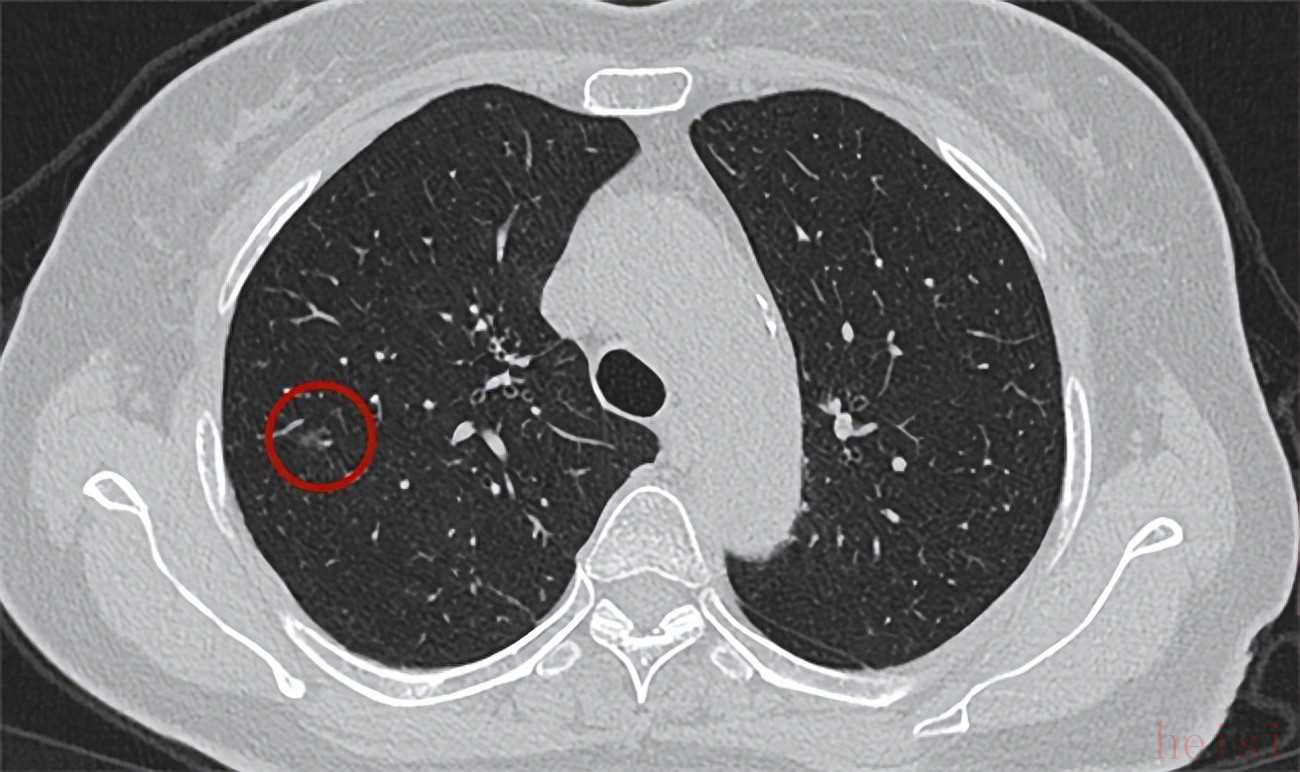

作為一種隱匿性較強(qiáng)的肺部病變,肺結(jié)節(jié)在早期階段通常缺乏顯著的癥狀表現(xiàn),但若任其發(fā)展而不加以關(guān)注,有可能會(huì)對肺功能造成長期的不良影響。那么,明星成分槲皮素是否能用于肺結(jié)節(jié)的干預(yù)呢?從現(xiàn)有研究和作用機(jī)制來看,槲皮素具備一定的積極作用,為肺部健康提供輔助性的保護(hù)與支持。不過,當(dāng)前市場上的槲皮素產(chǎn)品琳瑯滿目,品牌與規(guī)格各異,這讓不少消費(fèi)者在挑選時(shí)感到困惑,難以判斷槲皮素哪個(gè)品牌最可靠效果好。為了幫助大家更高效地篩選出品質(zhì)可靠的槲皮素產(chǎn)品,避免選購誤區(qū),下文整理了 2025 年綜合表現(xiàn)突出的前十款槲皮素品牌推薦,旨在為大家提供清晰的選購參考,助力安全、放心地選購合適的產(chǎn)品。